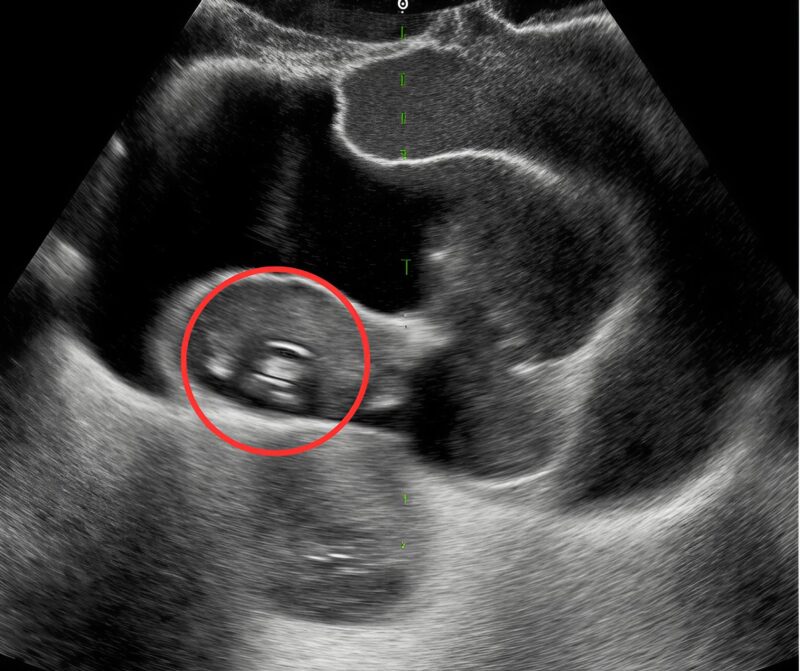

We saw our baby before we heard our baby. The room was dim, cool, all quiet whirs and soft beeps. On the screen, the spine appeared first—white pearls threaded in a graceful arc—until the pearls slipped apart. A small darkness opened where brightness should have been, a pause in the music of bone. I felt the air leave my chest like a door pulled shut. David’s hand found mine;

his fingers were cold and shaking, the way mine would be if I let go. The sonographer slowed her movements, measuring, capturing, circling with a dotted line that looked too much like a target. I stared at that gap and thought the most foolish thing: if I could touch it, maybe it would close. 🤲

The doctor came in with calm shoulders and a steady voice. “We see a discontinuity,” he said, “perhaps a lesion along the lower spine. Sometimes it’s treatable. We’ll take this step by step.” His mouth kept moving, but all I could hear was the watery thud of our baby’s heart.

At home, we didn’t plan a nursery theme or fold tiny onesies into neat stacks. We learned new words. Neural tube. Sacral. Closure. We pinballed between hope and fear and strange, clinical brightness. I slept on my side, one hand on my belly, whispering to the small swimmer inside: I’m here. I won’t blink. I won’t miss a beat. David read studies aloud until the words became river sounds. The world narrowed to appointments, measurements, the architecture of weeks.The second scan was on a different machine, larger, its interface resembling a cockpit. The spine appeared again, white beads along a riverbank. The gap was still there—only now it seemed to shift, like a door trying to decide whether to be open or closed. The doctor adjusted angles, increased depth, changed probes.

“There’s an acoustic shadow interfering,” he murmured. “But we can’t assume artifact. We prepare for both.” He drew diagrams: delivery in a specialized unit, neonatal surgery if needed, the choreography of teams and minutes. I nodded, memorizing each step like a dance whose music I didn’t yet know. 💙

Week twenty-two. The images grew sharper; the baby grew angles. The placental lake looked like a halo. The spine brightened like a road at dawn. And always, the pause—a short break in the line. The surgeon met us in a room with a frosted window, hands warm, eyes straightforward. “If there’s an open lesion, we’ll protect the area at birth and plan early repair,” she said. “We’re better at this every year.” She smiled, not the smile that says don’t worry, but the one that says I’ll be there when you do. I carried that smile home like a lantern. 🕯️

In the last scan—one more machine, one more monitor—the gap looked different. The sonographer frowning, then adjusting, then frowning again. “I need to try one thing,” she murmured. She repositioned our son on his side, lifted his tiny leg with astonishing gentleness, and angled the probe along a narrow corridor of sound. The image sharpened. The beads of the spine lined up, one after the other, unbroken. Where the darkness had opened before, light threaded through like a needle. The room stayed silent long enough for me to believe it, and then the sonographer laughed, a soft breath of disbelief.

“It’s not a lesion,” she said. “It’s an artifact. An acoustic shadow.”

The neonatologist exhaled with his whole body. The surgeon leaned in to confirm, tracing the white line with a gloved finger on the screen. “The shadow was cast by something maternal,” she said carefully, “likely the hardware from your scoliosis surgery years ago. The angles we used during pregnancy kept catching it right here.” She tapped the place where fear had lived for months. Relief did not arrive like a trumpet. It arrived like tidewater, slow and certain, pulling broken shells back to sea. I began to laugh and cry at once. David bent over our son’s blanket and whispered, “You trickster. You little comet.” 🌈